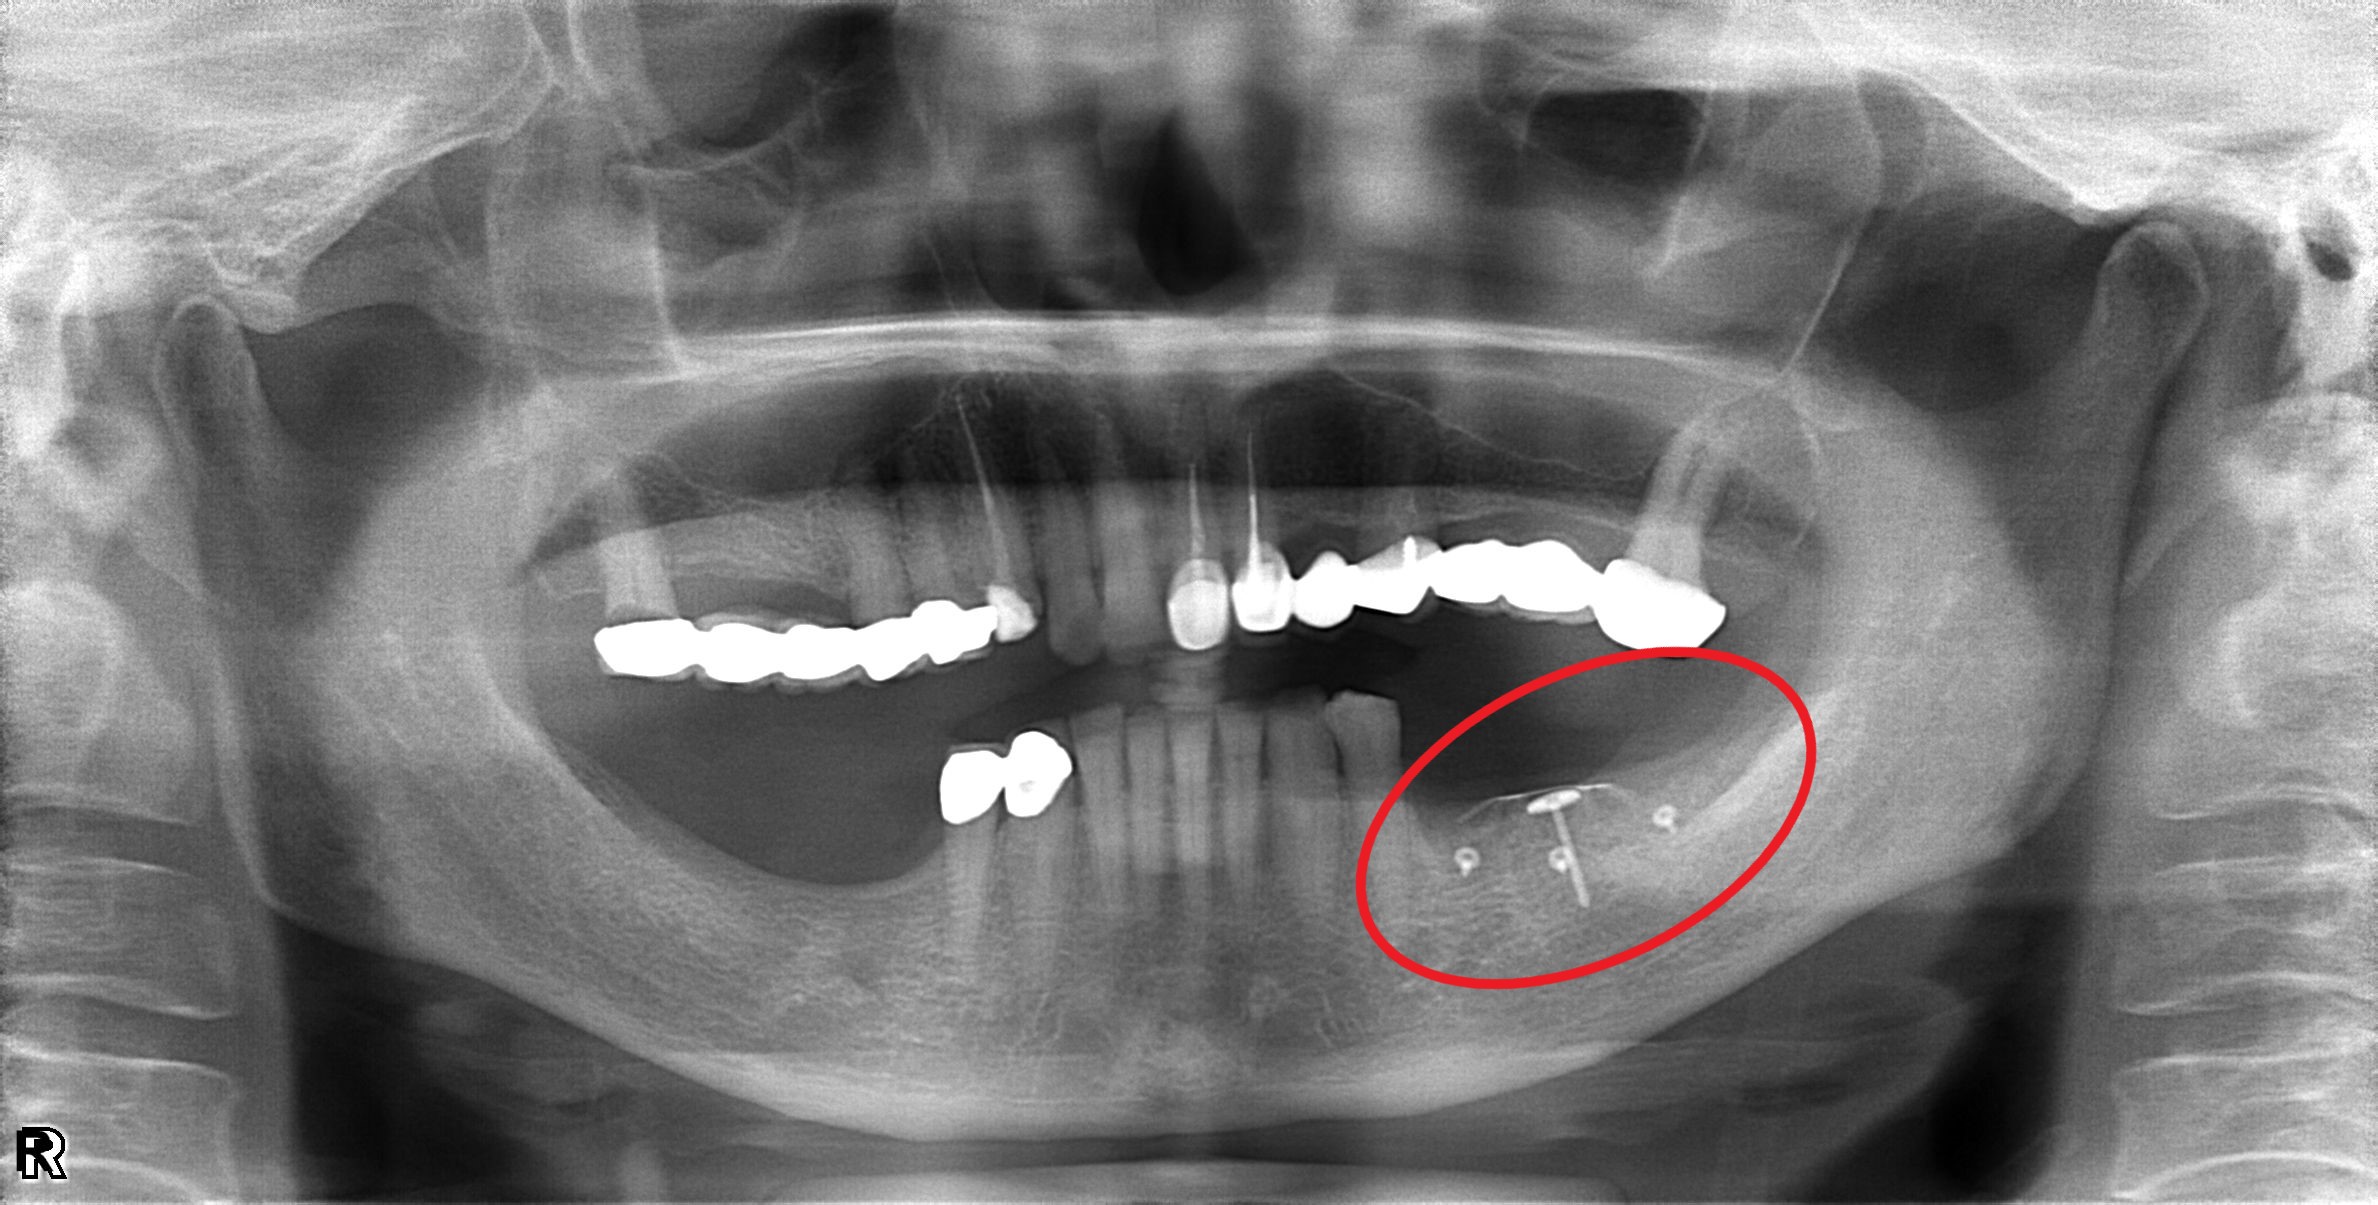

案例四

缺牙造成齒槽骨流失

翻瓣補骨的區域,先擷取所需不可吸收骨膜的大小,用骨釘固定

*不可吸收骨膜:不會被身體吸收、需要再開刀取出的膜,放在補骨區用來隔離軟組織並撐住空間,讓骨粉有足夠時間生長成新骨

補入所需骨粉

最後縫合傷口,等待癒合

完成後依骨頭恢復裝況,需定期回診給醫生評估是否進行下一個階段